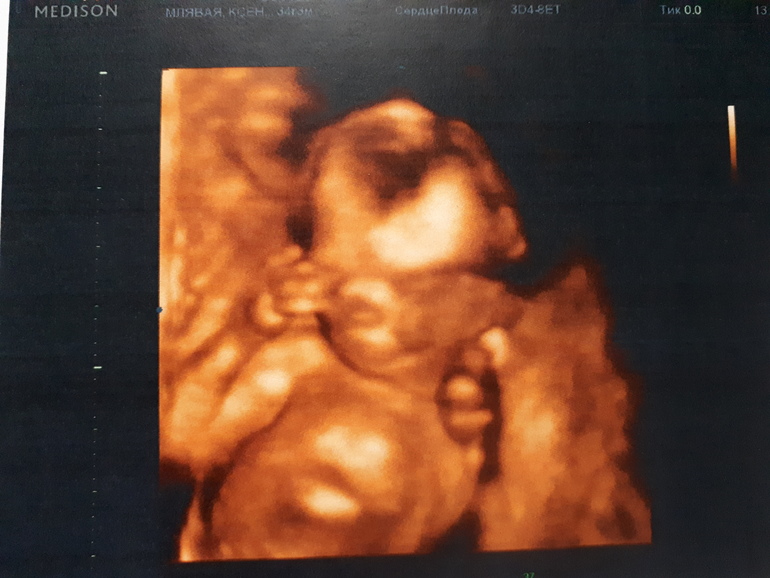

Ходила в 16 недель, нам записывали, но особо интересного ничего не запечатлели, поэтому даже врач сказала что не стоит брать. Сделали пару фоток и всё. Пойду в 25 недель примерно еще. С дочкой в 24 недели записывала, там уже поинтересней было. Вот фотка 16 недель.